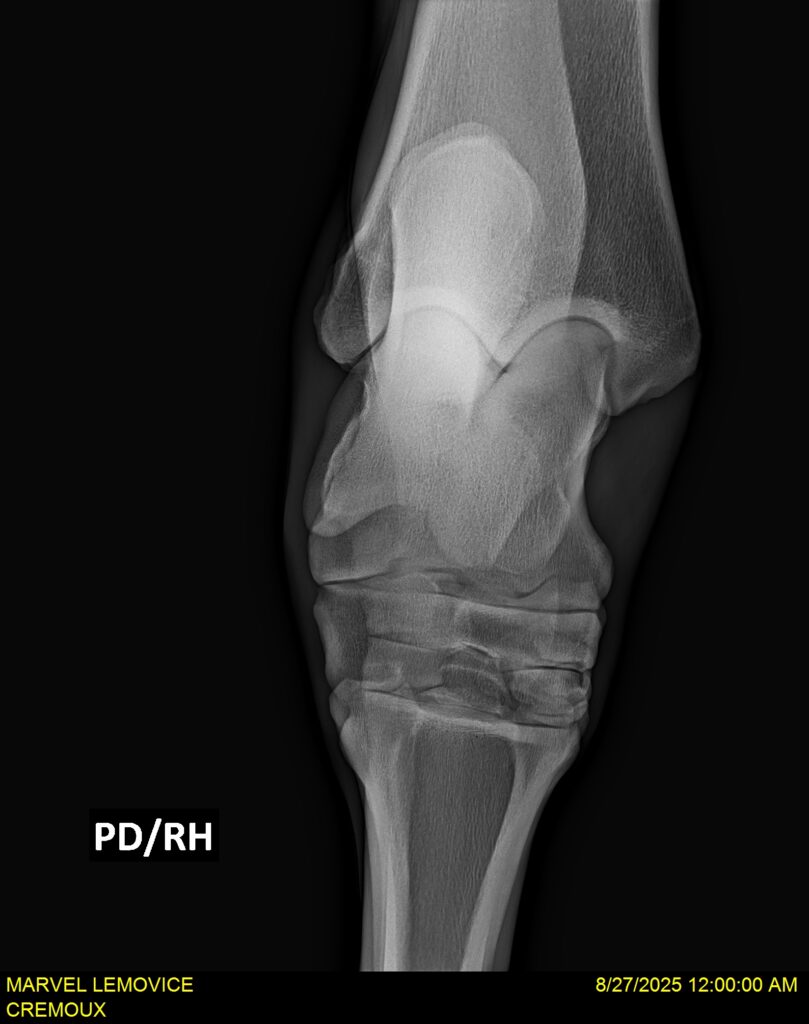

MARVEL LEMOVICE, hongre, Selle Français prend 4 ans en 2026. POPSTAR LOZONAIS x ROSIRE sur une excellente souche maternelle de l’élevage PLATIERE. Débourré aux trois allures et mise en route à l’obstacle. Super modèle avec du cadre et de la force, cheval respectueux avec des moyens. Très agréable au quotidien. Transport OK, maréchalerie OK, santé RAS, Bilan 20 clichés radios + clinique OK.

RADIOS ET CLINIQUE